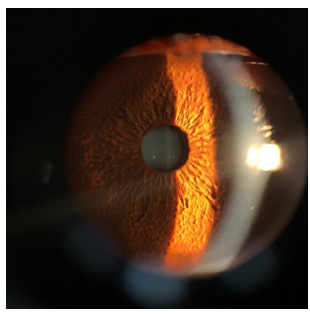

Clinical Image

Anterior Capsulophimosis Contraction Syndrome

Farah Benlkadri, Basma Ouidani, El Mehdi El Filali, Youssef Bennouk, Hussein Ait lhaj, Mohamed Kriet and Fouad Elasri. 14(9): 01.